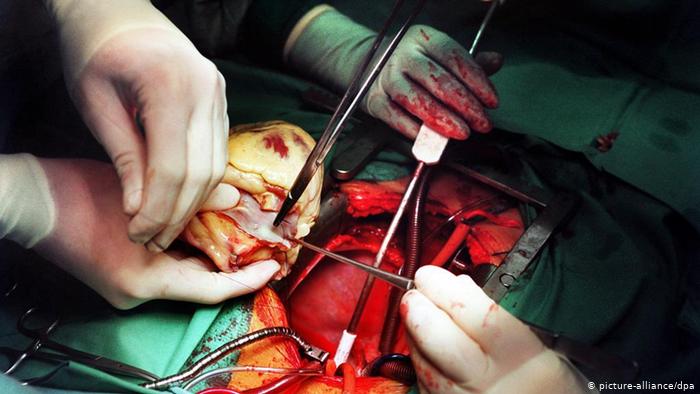

عملية القلب المفتوح

كان الأطباء يرغمون على إيقاف عمل الدورة الدموية في الجسم عند إجراء عملية جراحية في القلب. ولكن في خمسينات القرن الماضي اكتشف الجراحون طريقة جديدة مكنتهم من حل المشكلة عن طريق استعمال جهاز يستخدم مؤقتا إثناء العملية الجراحية ويقوم بتزويد الدم بالأوكسجين ومن ثم إرساله إلى باقي الجسم، وفي هذه الحالة يقوم الجهاز بعمل القلب والرئة معاً.